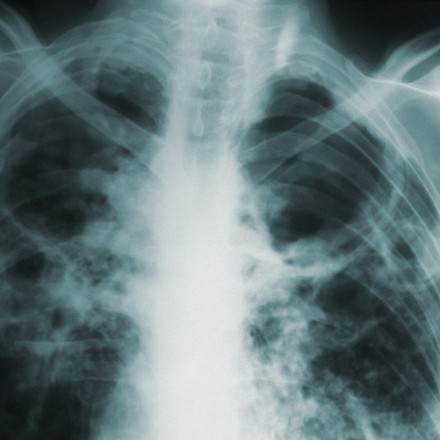

«Η ζωή με την άγνωστη – γνωστή νόσο»: Η Ιδιοπαθής Πνευμονική Ίνωση που χτυπά τους 50άρηδες 20.09.2023 11:49 Αγγελική Γιαννακού